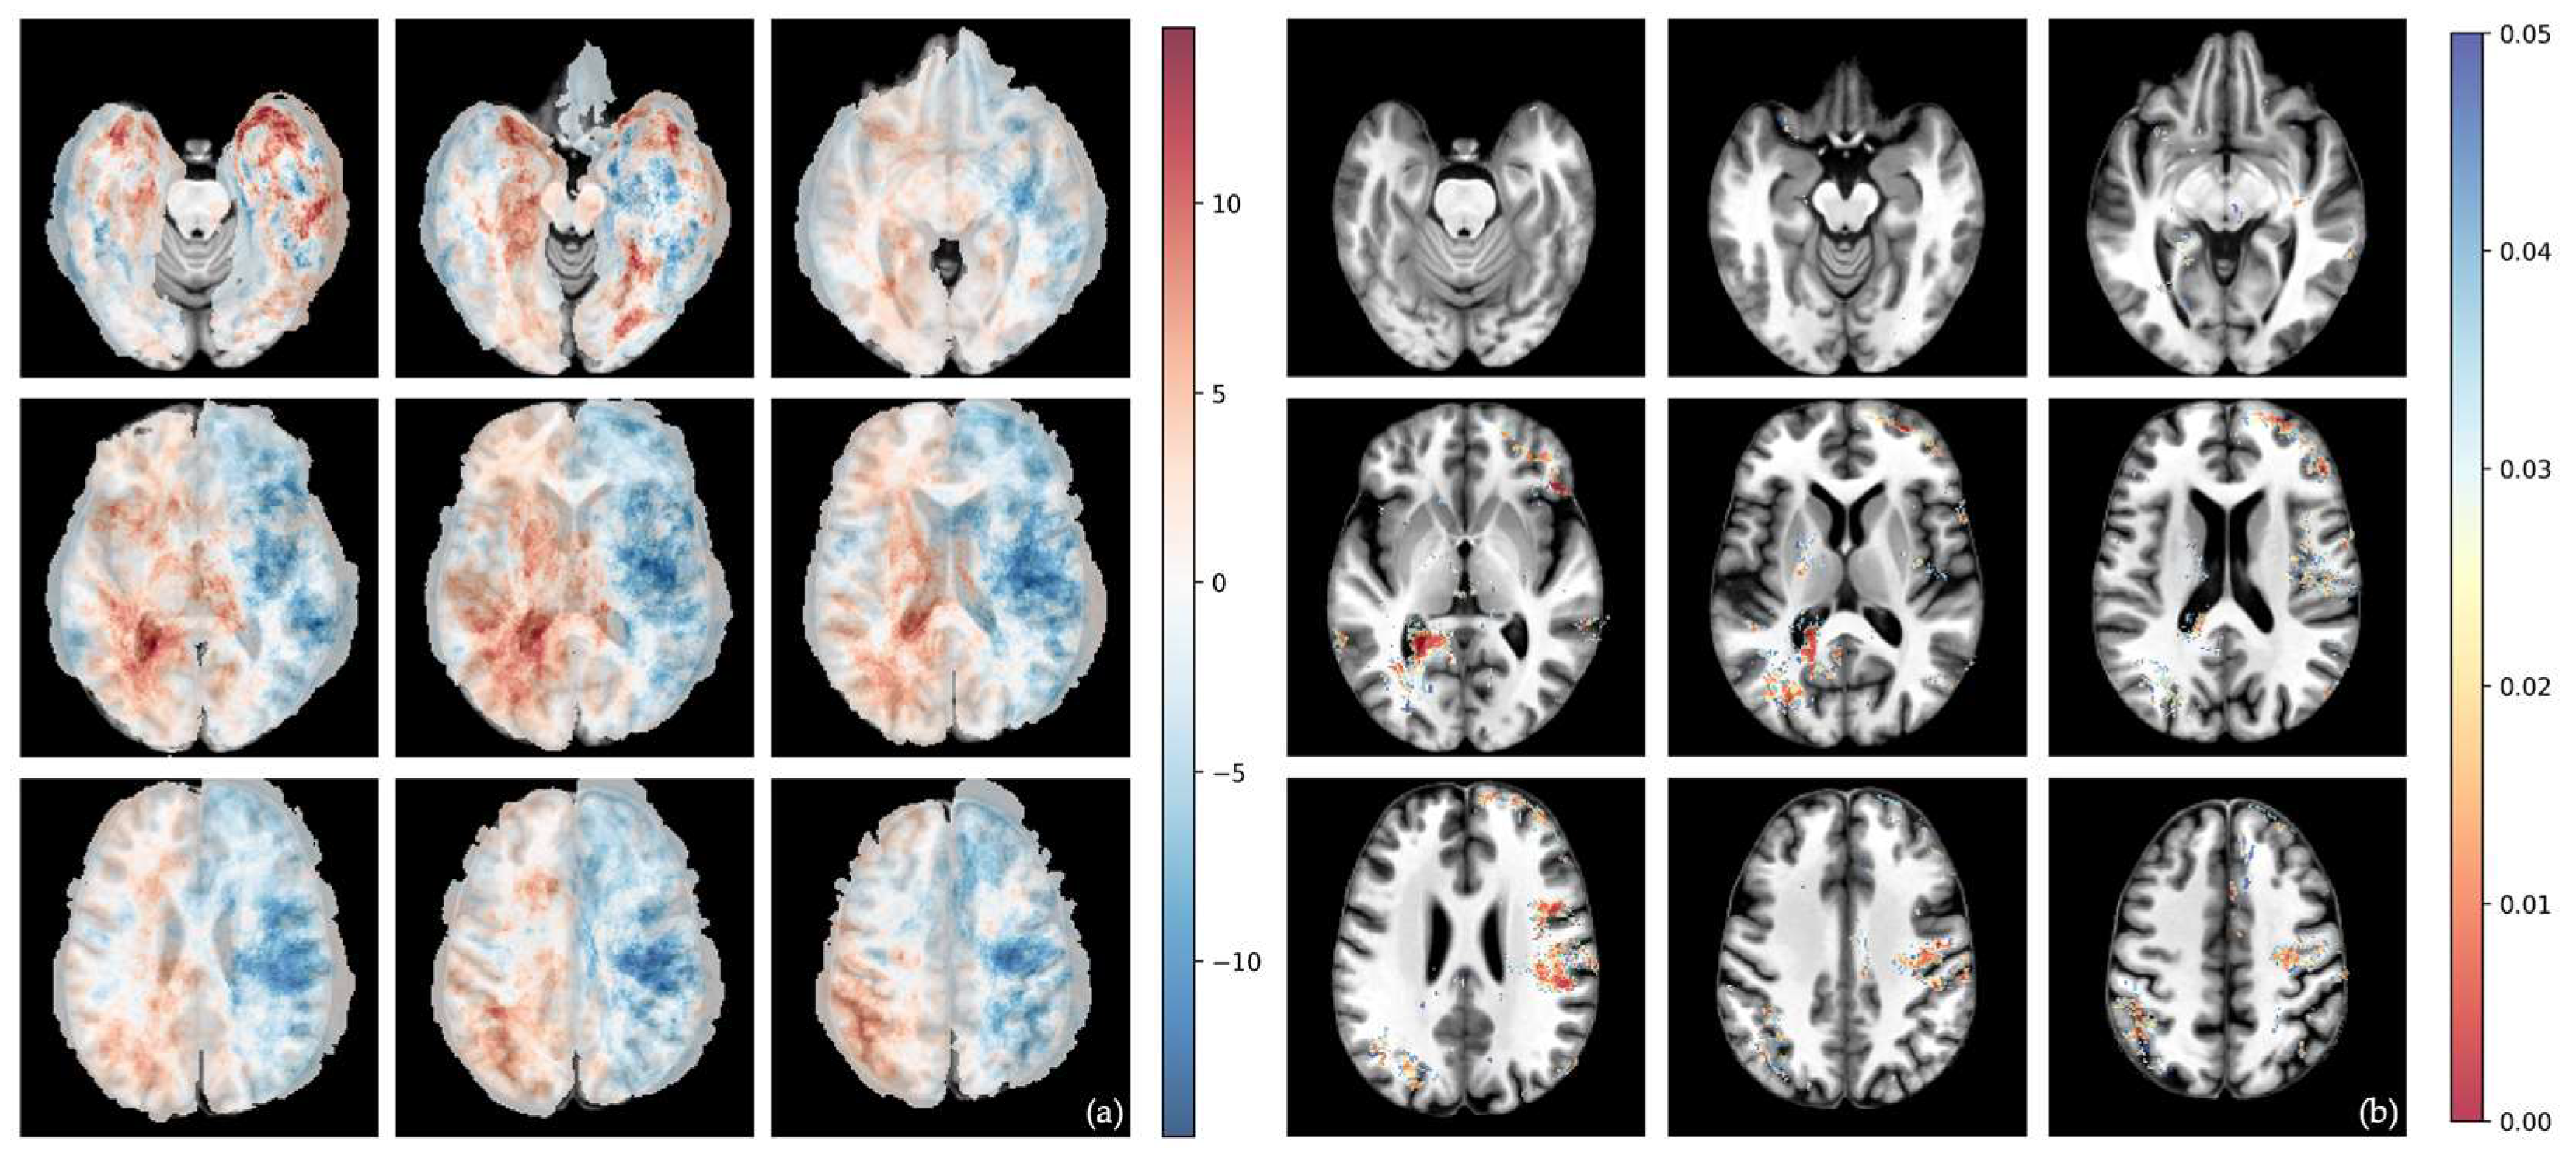

3.3. Voxel-Wise Analysis of Differential Involvement